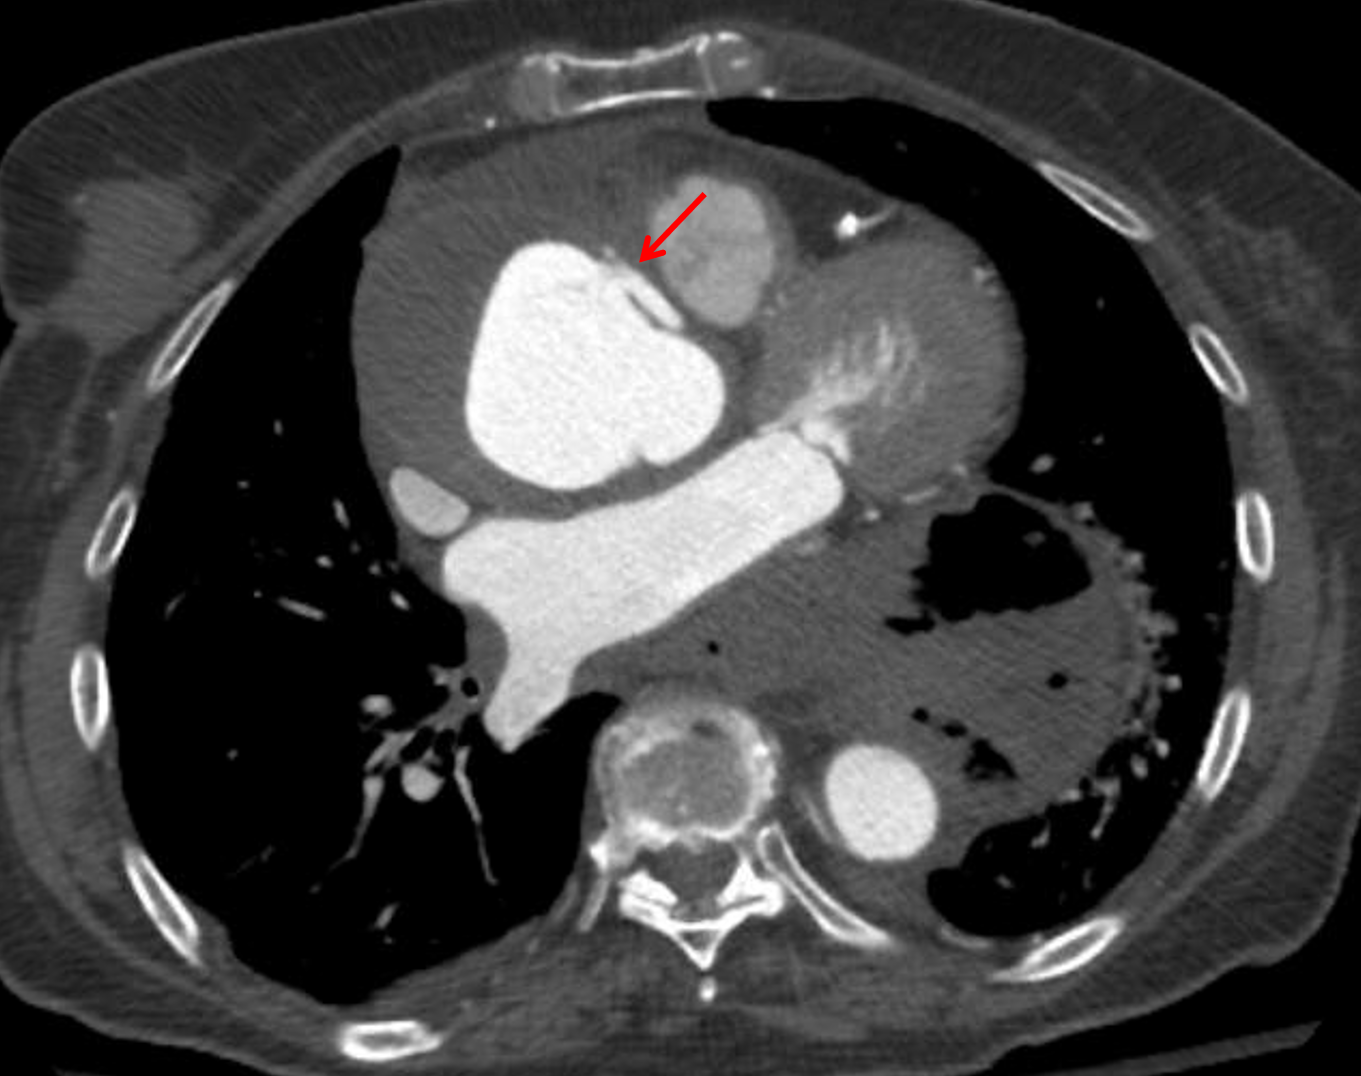

Sample ReportType A aortic dissection extending from the aortic root to the distal arch with associated small hemopericardium and aneurysmal dilation of the ascending aorta measuring up to 7 cm in diameter. The false lumen is largely thrombosed with extensive intramural hematoma extending into the origins of the brachiocephalic and left common carotid arteries, which remain widely patent. Recommend surgical evaluation.